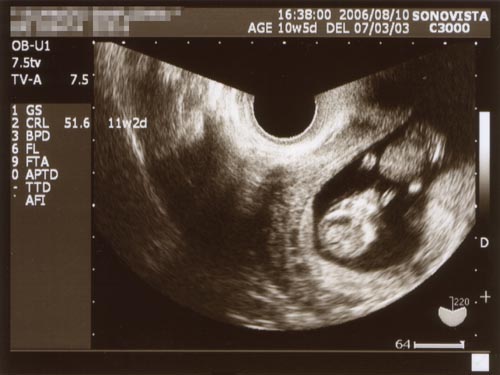

●2006.08.12(Sat)

というわけでわが子の成長ぶりを確認するべく、検診に行ってきました。

![]()

(クリックすると拡大します)

頭臀長はなんと51.6mm !!

じつに2週間で倍以上に成長しています!

すごい!

いったいお腹の中で何をしているんだろう・・・・・?